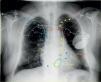

A 64-year-old male with idiopathic cardiomyopathy and atrial fibrillation, previously fitted with a cardioverter-defibrillator (ICD) using a persistent left superior vena cava (PLSVC) for lead placement, was scheduled for upgrade to a cardiac resynchronization therapy-defibrillator due to new-onset left bundle branch block, heart failure and severely depressed left ventricular (LV) ejection fraction. A selective venogram of the coronary sinus from a left-sided approach revealed a sharp angulation of a lateral subsidiary target vein, precluding placement of the LV electrode in an optimal position, and leading to non-controllable diaphragmatic stimulation. A solution was devised by accessing the right subclavian vein and culminating in subcutaneous tunneling of the lead to the contralateral generator pocket. A control chest X-ray with explaining diagram (Figure 1) shows the right ventricular defibrillator lead (yellow arrowheads and dashed yellow line) following a standard left subclavian vein (LSCV) approach but going through a PLSVC draining to the coronary sinus (CS), then entering the right atrium (RA) and crossing the tricuspid valve, with its tip abutting the right ventricular (RV) apex. The LV lead is seen sequentially entering (blue arrows) the right subclavian vein (RSCV), superior vena cava (SVC), RA, CS and lateral vein. Finally, the end of the proximal LV lead (asterisks) is tunneled subcutaneously and connected to the previously placed generator in a left prepectoral position.